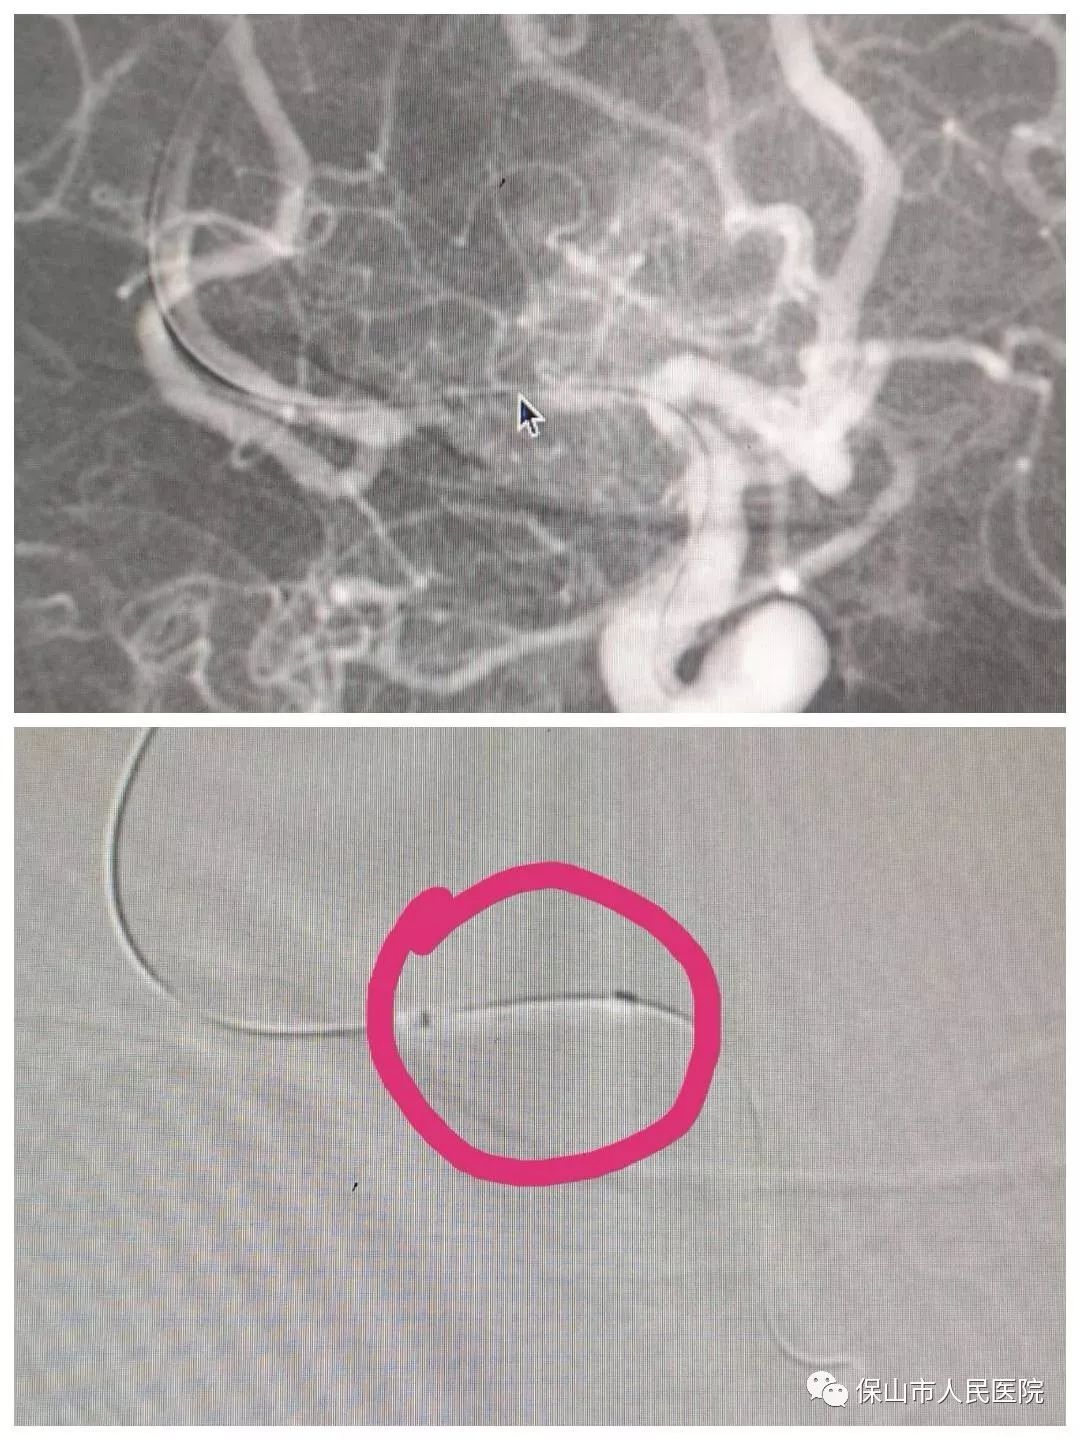

通過導絲(si) 和導管的配合,將支架放在狹窄的部位,如圖中兩(liang) 個(ge) 標記點之間,然後再釋放支架,把狹窄部位支撐開。

支架釋放之後,再次造影,對比前麵的視頻,很直觀的改變,狹窄部位已經被支架支撐開來,椎動脈裏麵的血流速度比之前加快不少。

另外一名患者情況相似,術中造影診斷為(wei) 右側(ce) 椎動脈開口狹窄,狹窄程度約70%,確定位置後,支架到位釋放。

支架植入前後對比,右側(ce) 椎動脈的狹窄部位也已經被支架撐開,椎動脈狹窄問題解決(jue) 。